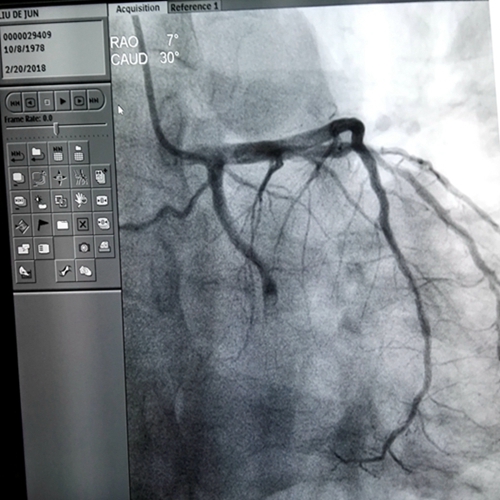

术前造影

接到电话后,范爱德副主任医师带领值班手术团队在最短时间内赶到手术室,在取得患者及家属同意后,17:20顺利完成冠脉造影+PCI术。造影显示:冠状动脉多支多处严重狭窄病变,其中左回旋支中段全部闭塞(考虑为本次心肌梗死的罪犯血管),球囊扩张后植入支架一枚,术后罪犯血管恢复正常血流灌注。整个手术顺利,从患者进入导管室到手术完毕仅用了1小时左右。